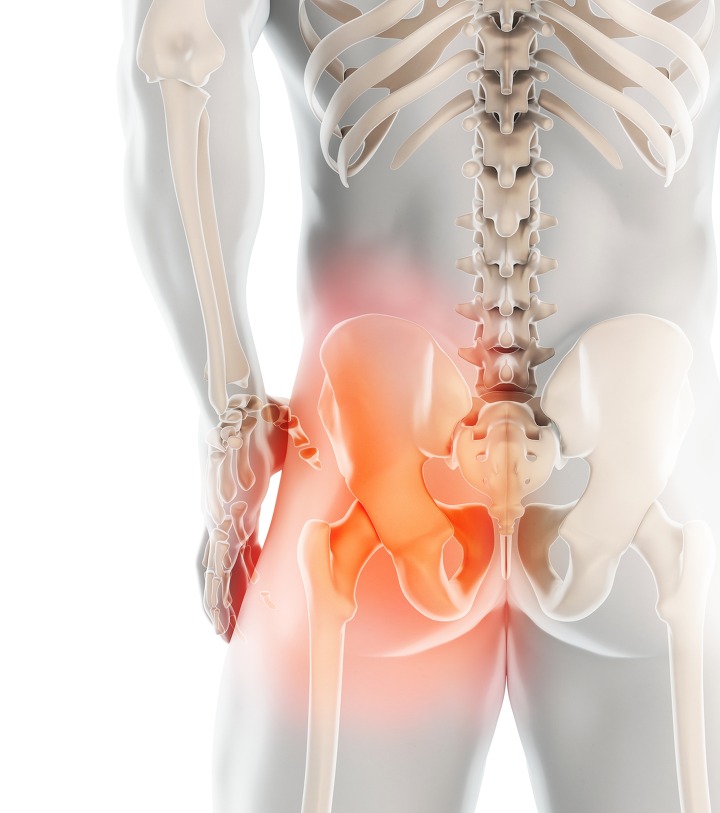

나쁜 자세 또한 고관절 통증을 일으키게 되는데 자세로 인한 통증은 주로 한쪽에 나타납니다. 한쪽에 체중이 실리면 그쪽 고관절이 아플 수 있으니 다리꼬기, 짝다리 짚기, 비딱하게 앉기 등을 주의하셔야 합니다.. 책상다리 또는 양반다리라고 하는 자세도 삼가하는 것이 좋습니다.

고관절 통증 증상 11.평소 자세 불량

학생 및 운전을 많이 하는 사람 그리고 회사원처럼 온종일 계속 앉은 상태로 업무를 하는 사람들은 인대와 굴곡근 및 근처에 있는 연부조직들과 뼈를 들어주고 있는 중요한 기관들이 힘을 잃어서 약해지게 됩니다. 계속 앉아있으면서 불편한 자세가 지속되면서 고관절 통증을 유발할 수 있습니다.